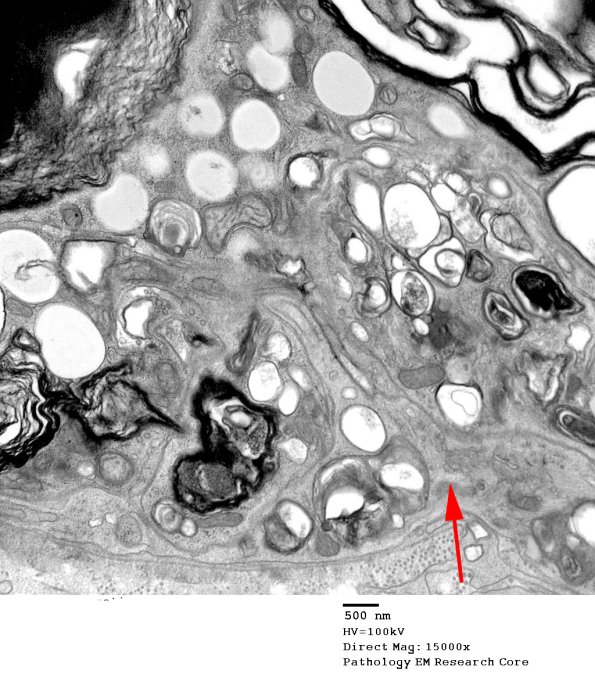

In this image the macrophage process (arrow) has traversed the Schwann cell basal lamina and has begun removing debris.